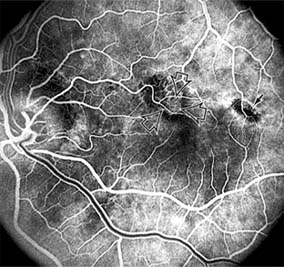

Presumed Ocular Histoplasmosis Syndrome (Figures 10-5, 10-6 and 10-7)

In this disease, serous and hemorrhagic detachments of the macula are associated with multiple peripheral atrophic chorioretinal scars and peripapillary chorioretinal scarring (see Chapter 7). The syndrome usually occurs in healthy patients between the third and sixth decades of life, and the scars are probably caused by an antecedent subclinical systemic infection with Histoplasma capsulatum. The macular detachments are due to subretinal neovascularization, and the visual prognosis depends on the proximity of the neovascular membrane to the center of the fovea. If the membrane extends inside the foveal avascular zone, only 15% of eyes will retain 20/40 vision. A macular scar may change over time, and 10% of patients with normal maculae will develop new atrophic scars in this region. The relative risk of developing macular subretinal neovascularization in the second eye of an affected patient is significant, and these patients should be instructed in the frequent use of the Amsler grid and the importance of prompt examination when changes are detected.

Figure 10-6

Figure 10-6: The early fluorescein angiogram shows an inactive hypofluorescent scar (small arrow) and the characteristic lacy hyperfluorescence of subretinal neovascularization (open arrows).

Figure 10-7

Figure 10-7: Late fluorescein leakage from macular subretinal neovascularization in a patient with presumed ocular histoplasmosis syndrome.